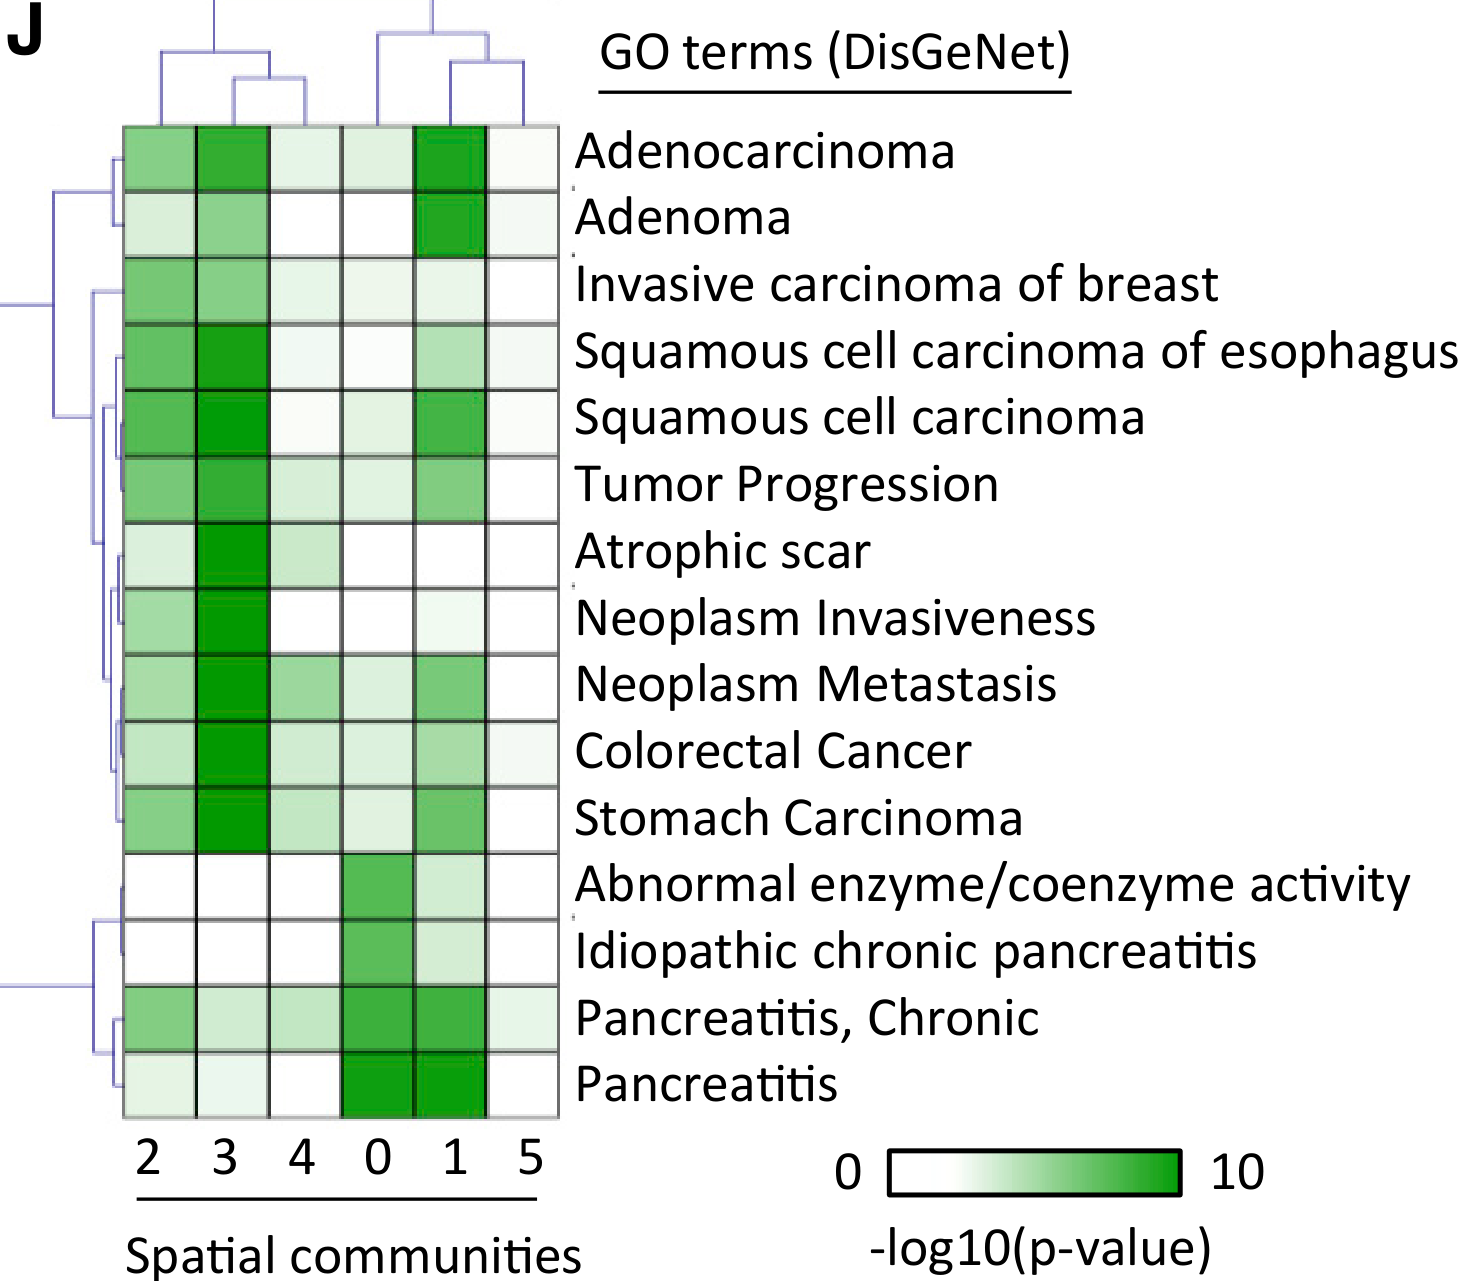

Which cancer-related pathways are enriched in different tumor regions?